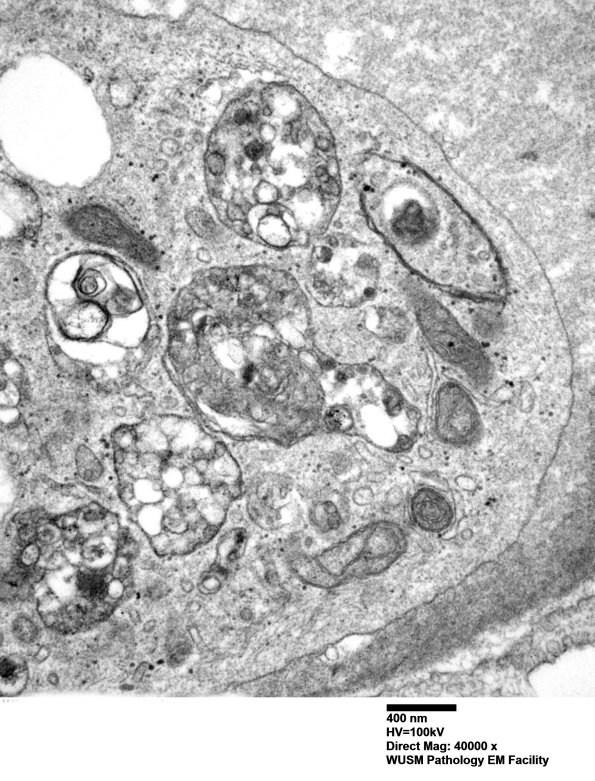

These are most likely autophagic vacuoles in the perineurial interstitium. (electron micrographs)